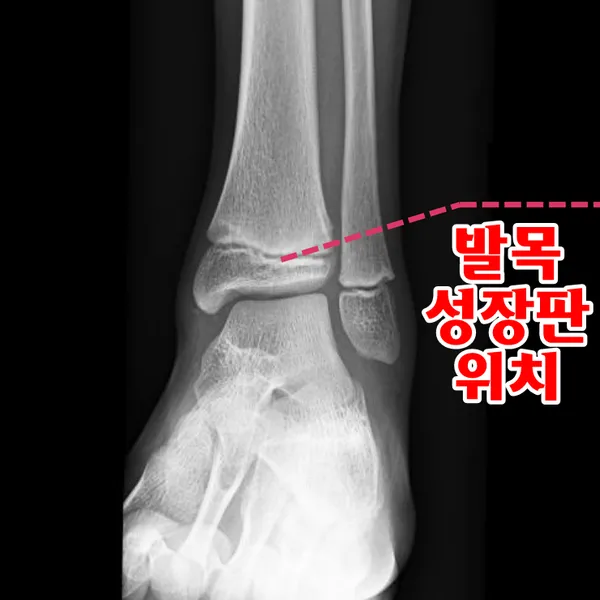

성장판은 하나의 문이 갑자기 '딱' 닫히는 것이 아닙니다. 손가락, 발가락, 손목, 발목, 골반, 척추 순으로 뼈 끝 쪽의 연골이 굳어져 가는 과정은 꽤 오랜 시간이 걸려요. 성장판의 닫히는 시기는 개인차가 매우 크답니다.

일반적으로 여성은 14-15세, 남성은 16-17세에 성장판이 닫히기 시작하지만, 완전히 닫히는 것은 만 19-20세경이에요. 하지만 여기서 중요한 건, 성장판 검사에서 '닫혔다'고 나와도 검사 오차가 있을 수 있고, 미세하게 남아있는 성장판으로 인한 성장 가능성이 남아있다는 점입니다.